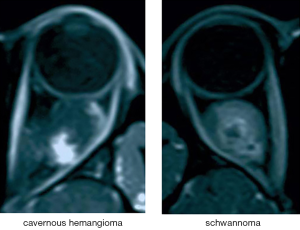

Based on clinical experience, T1-weighted contrast-enhanced sequences can highlight the blood vessels. Progressive filling from center to periphery on enhancement is typical of cavernous hemangioma, while the enhancement pattern of schwannoma is partial and uneven (5,6) (see Figure 4). Therefore, these sequences are considered the most significant reference among all types of slices in the differential diagnosis of the two studied tumor types (23,24). The tumor classification model trained by the transverse T1-weighted contrast-enhanced sequence images and tested on the external validation sets achieved high accuracy, sensitivity, and specificity in automated cavernous hemangioma and schwannoma differential diagnosis in a real-world setting that is completely consistent with the clinical environment.